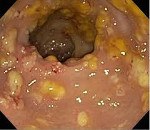

K52.8.0* Колит псевдомембранозный